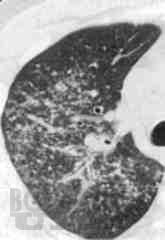

В учебно-методическом пособии авторы представили данные об этиологии, патогенез, патологической анатомии саркоидоза, клинико-рентгенологические классификации, методы диагностики лабораторные, лучевые (рентгенография, томография, КТ, МРТ, ПЭТ), радиоизотопное, бронхологические особенности современного саркоидоза. Приведены примеры собственных наблюдений.